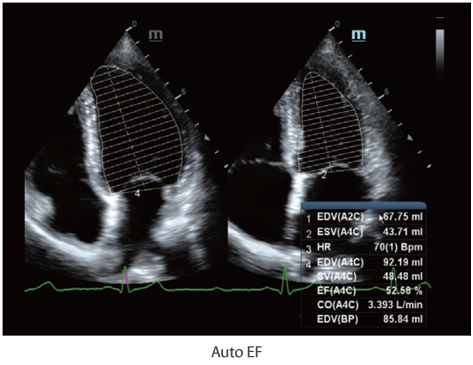

–ú–Ĺ–ĺ–≥–ĺ—Ą—É–Ĺ–ļ—Ü–ł–ĺ–Ĺ–į–Ľ—Ć–Ĺ–į—Ź —Ā–ł—Ā—ā–Ķ–ľ–į DC-60 Exp —Ā X-Insight –Ņ—Ä–Ķ–ī—Ā—ā–į–≤–Ľ—Ź–Ķ—ā —Ā–ĺ–Ī–ĺ–Ļ –ļ–ĺ–ľ–Ņ–Ľ–Ķ–ļ—Ā–Ĺ–ĺ–Ķ —Ä–Ķ—ą–Ķ–Ĺ–ł–Ķ, –ļ–ĺ—ā–ĺ—Ä–ĺ–Ķ –Ņ–ĺ–ľ–ĺ–≥–į–Ķ—ā —É–Ņ—Ä–į–≤–Ľ—Ź—ā—Ć –Ņ–ĺ–≤—Ā–Ķ–ī–Ĺ–Ķ–≤–Ĺ–ĺ–Ļ –ļ–Ľ–ł–Ĺ–ł—á–Ķ—Ā–ļ–ĺ–Ļ –Ņ—Ä–į–ļ—ā–ł–ļ–ĺ–Ļ —Ā –Ľ–Ķ–≥–ļ–ĺ—Ā—ā—Ć—é –ł —É–≤–Ķ—Ä–Ķ–Ĺ–Ĺ–ĺ—Ā—ā—Ć—é.

–ě—Ā–Ĺ–ĺ–≤—č–≤–į—Ź—Ā—Ć –Ĺ–į –≥–Ľ—É–Ī–ĺ–ļ–ĺ–ľ –Ņ–ĺ–Ĺ–ł–ľ–į–Ĺ–ł–ł –Ņ–ĺ—ā—Ä–Ķ–Ī–Ĺ–ĺ—Ā—ā–Ķ–Ļ –ļ–Ľ–ł–Ķ–Ĺ—ā–ĺ–≤, –ļ–ĺ–ľ–Ņ–į–Ĺ–ł—Ź Mindray —Ä–į–∑—Ä–į–Ī–ĺ—ā–į–Ľ–į —Ā–ł—Ā—ā–Ķ–ľ—É DC-60 Exp —Ā X-Insight, —á—ā–ĺ–Ī—č –ĺ–Ī–Ķ—Ā–Ņ–Ķ—á–ł—ā—Ć –≤—č—Ā–ĺ–ļ—É—é –Ņ—Ä–ĺ–ł–∑–≤–ĺ–ī–ł—ā–Ķ–Ľ—Ć–Ĺ–ĺ—Ā—ā—Ć –ł —ā–ĺ—á–Ĺ–ĺ—Ā—ā—Ć –≤–ł–∑—É–į–Ľ–ł–∑–į—Ü–ł–ł –≤–ļ—É–Ņ–Ķ —Ā –Ĺ–į–≥–Ľ—Ź–ī–Ĺ–ĺ—Ā—ā—Ć—é, –ł—Ā–ļ–Ľ—é—á–ł—ā–Ķ–Ľ—Ć–Ĺ–ĺ–Ļ –ł–Ĺ—ā–Ķ–Ľ–Ľ–Ķ–ļ—ā—É–į–Ľ—Ć–Ĺ–ĺ—Ā—ā—Ć—é –ł –ĺ–≥—Ä–ĺ–ľ–Ĺ—č–ľ –ĺ–Ņ—č—ā–ĺ–ľ.